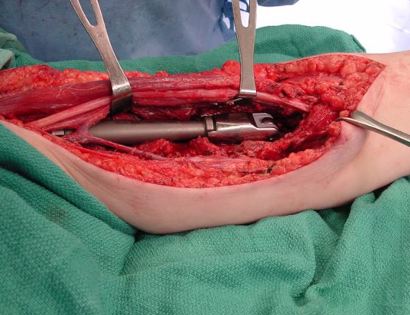

Intra-Op: Blood Vessel and Nerve Dissection

This is an image of the arm after an incision was made to pull back the skin. The tumor is underneath the muscular tissue causing the raised muscle seen in the photo.